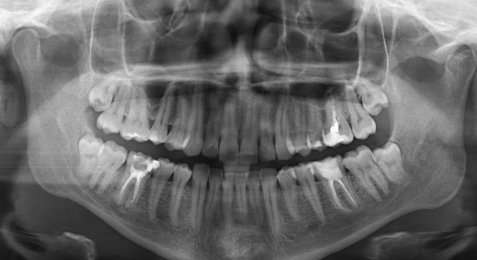

Обращалась к врачам по поводу боли при надкусывании на семерку сверху. Ответ у всех разный. Одни причину ставят - зуб мудрости под десной, который давит на семерку и его надо удалять, другие - больная семерка, а один врач сказал, что никакой восьмерки сверху у меня нет. Я в растерянности.

Я вам уже ответил, боль в седьмом зубе связана с хроническим воспалением на верхушках данного зуба. Обратитесь на очный прием в стоматологическую клинику. Мост необходимо снимать и перелечивать опорные зубы.